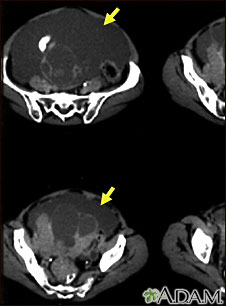

Tomografía computarizada de ascitis con cáncer ovárico

Ascitis con cáncer ovárico; TC

Esta tomografía computarizada de la parte baja del abdomen muestra una cantidad enorme de líquido abdominal libre (ascitis) en una paciente con cáncer de ovario.